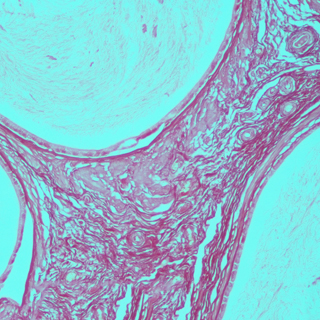

實(shí)驗(yàn)結(jié)果:

脂滴呈橘紅色至鮮紅色:細(xì)胞核呈深藍(lán)色。